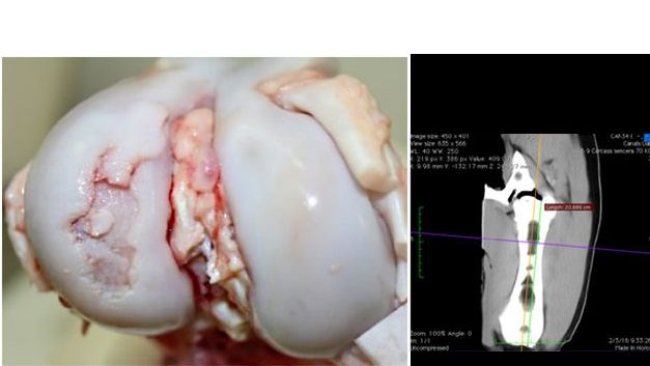

El presente artículo revisa el efecto de componentes de la dieta sobre el hueso y la osteocondrosis, principal causa de cojeras y motivo de eliminación de reproductoras jóvenes. Por lo tanto, conceptos importantes a tener en cuenta en las dietas para recría de nulíparas.

¿Una elevada velocidad de crecimiento realmente aumenta el riesgo de osteocondrosis y cojeras?